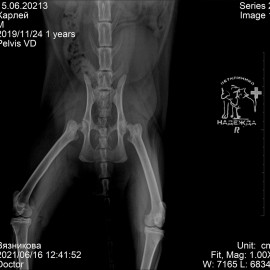

Была проведена операция: резекционная артропластика тазобедренных суставов.

Снимок после операции: